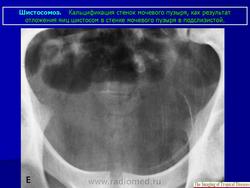

Бильгарциоз (Schistosomiasis) мочевого пузыря